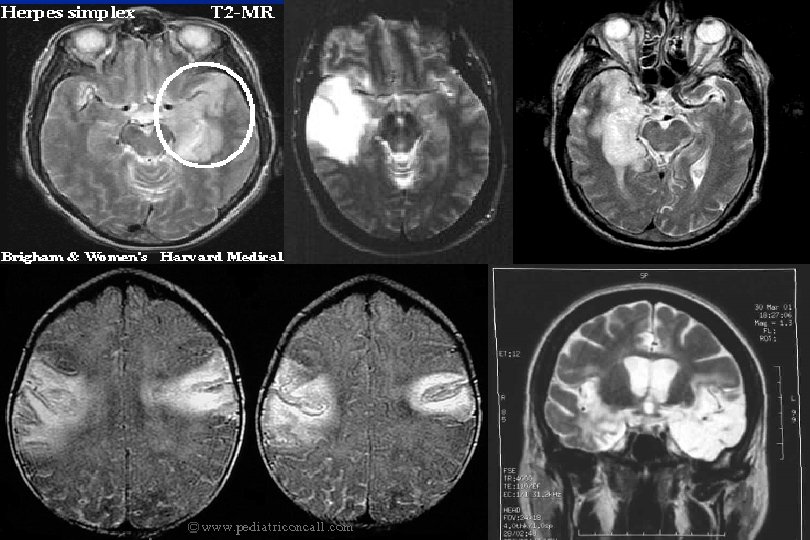

Herpes Ensefaliti Akut ensefalitlerin en sık ve fatal olanı l Trigeminal gangliyonda latent l İmmundüşkünlerde reaktivasyon l Temporal korteks ve limbik sistemi tutar l immündüşkün hastalarda aktif mükokutanöz HSV infeksiyonu l

Herpes Ensefaliti Yüksek ateş (% 89) l Baş ağrısı (% 78) l Bilinç değişlikliği/uykuya eğilim(% 96) l Kişlilik değişikliklikleri(% 61) l Epileptik nöbetler l Disfazi l Hemiparezi l Papilla ödemi l

HSVE’de tanı l l l Ø BOS’da 10 -2000/mm 3 hücre sayısı(lenfosit) Proteinde artış(7 -750) Normal/hafif düşmüş glikoz, sıklıkla eritrosit BOS da PCR yüksek özgüllük ve duyarlılığı BOS da HSV antikorları 2. haftadan sonra artar Tipik EEG bulguları 8 saatte bir 10 -15 mg/kg asiklovir(14 -21 gün)

HSVE’de MR İnferior temporal loblardaki hiperintens alanlar l Frontal ve pariyetal lobları da tutabilir l Bilateral temporal lob tutulumunun tanıda patognomonik olduğu bildirilmiş. l Lezyonlar ödem ve hemorajik enfarkt içerebilir l Erken dönemde MR bulguları normal olabilmektedir l